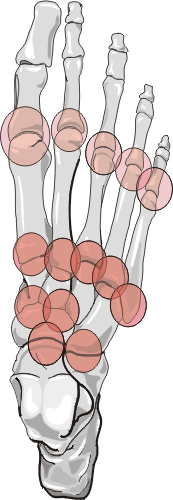

Distribution:

Bilateral metatarsophalangeal joint involvement is common, especially among diabetics. The second tarso metatarsal joint is a frequent site for early subluxations. Mono- or polyarticular interphalangeal joint or midfoot presentations may also occur.